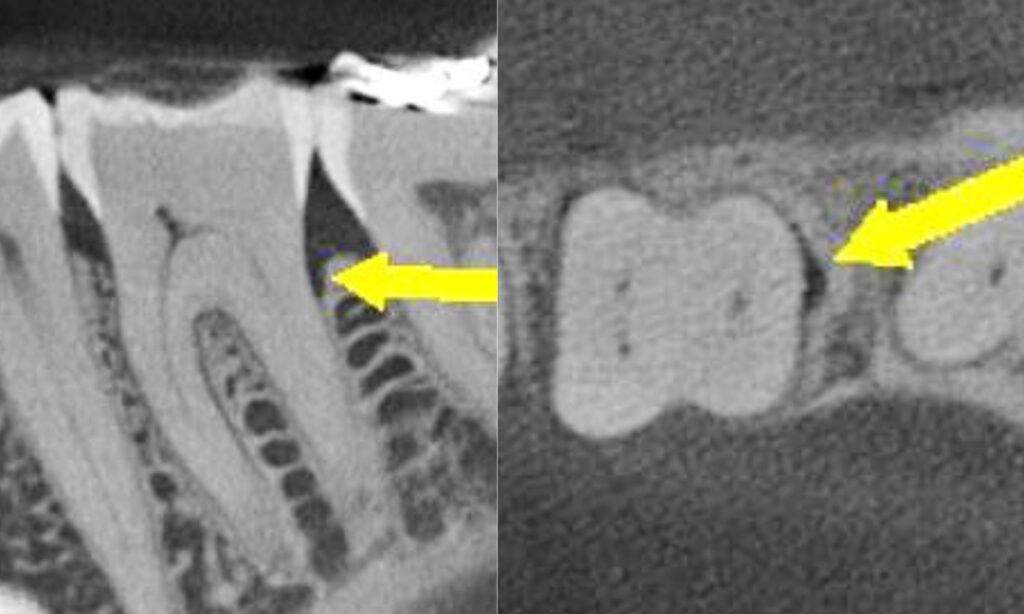

Will you see the crack? Probably not. But you may see periapical changes if the pulp’s been compromised. Standard radiographs? Usually inconclusive. Cracks like to stay off the radar but don’t dismiss them outright — check the crestal bone levels, particularly in the axial view. A subcrestal crack can trigger vertical bone loss that gives the game away, hidden intrabony defects, and isolated bone loss, are subtle signs that something’s wrong beneath the surface. This can give you an idea of the extent of the fracture and help determine the likely prognosis for treatment.